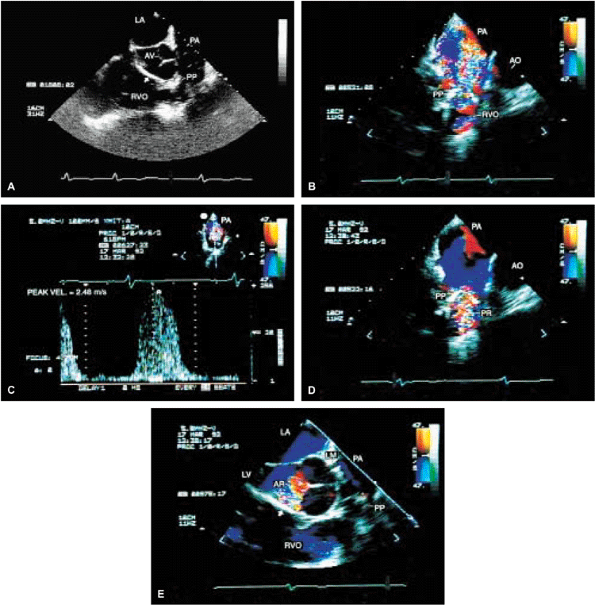

FIGURE 5.52. Pulmonary valve prosthesis. A prosthesis (PP) is shown in the pulmonary position in this patient, who also had repair of a ventricular septal defect (arrows inA,E). B. Turbulent flow (arrow) in the pulmonary artery (PA) in systole. The peak velocity by continuous wave Doppler measured 2.48 m/sec (C), which is within normal limits for a prosthetic valve. D. Associated severe pulmonary regurgitation (PR) is shown. E. This patient also had moderate aortic regurgitation (AR). AO, aorta; AV, aortic valve; LA, left atrium; LM, left main coronary artery; LV, left ventricle; RVO, right ventricular outflow tract. |